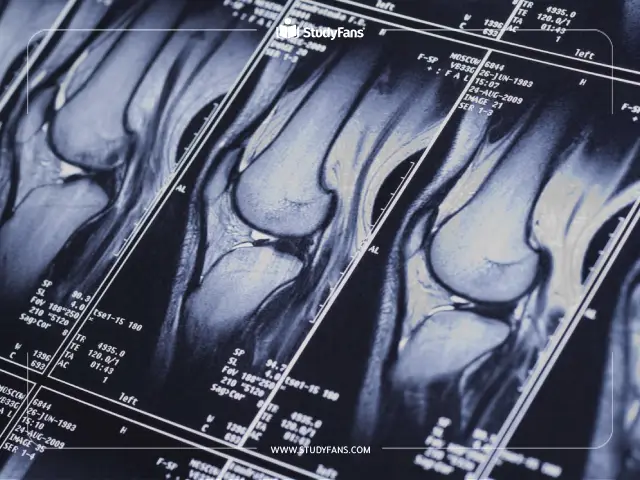

تعد دراسة طب الأشعة من أهم المجالات الدراسية التي يرغب الطلاب في دراستها، حيث يتلقون تدريبات نظرية وعملية شاملة، كما يكتسبون في الجامعات الماليزية المهارات اللازمة من أجل تشخيص الأمراض ومساعدة الأطباء في اتخاذ القرارات العلاجية الصحيحة.

حيث يعتمد كل قطاع في مجال الرعاية الصحية على طب الأشعة بما في ذلك: جراحة طب الأطفال، طب التوليد، علم الأورام الاستجابة للصدمة، كذلك في الأمراض المعدية، لذا توفر العديد من الجامعات الطبية المرموقة في ماليزيا أفضل البرامج الدراسية للطلاب.

الرنين المغناطيسي